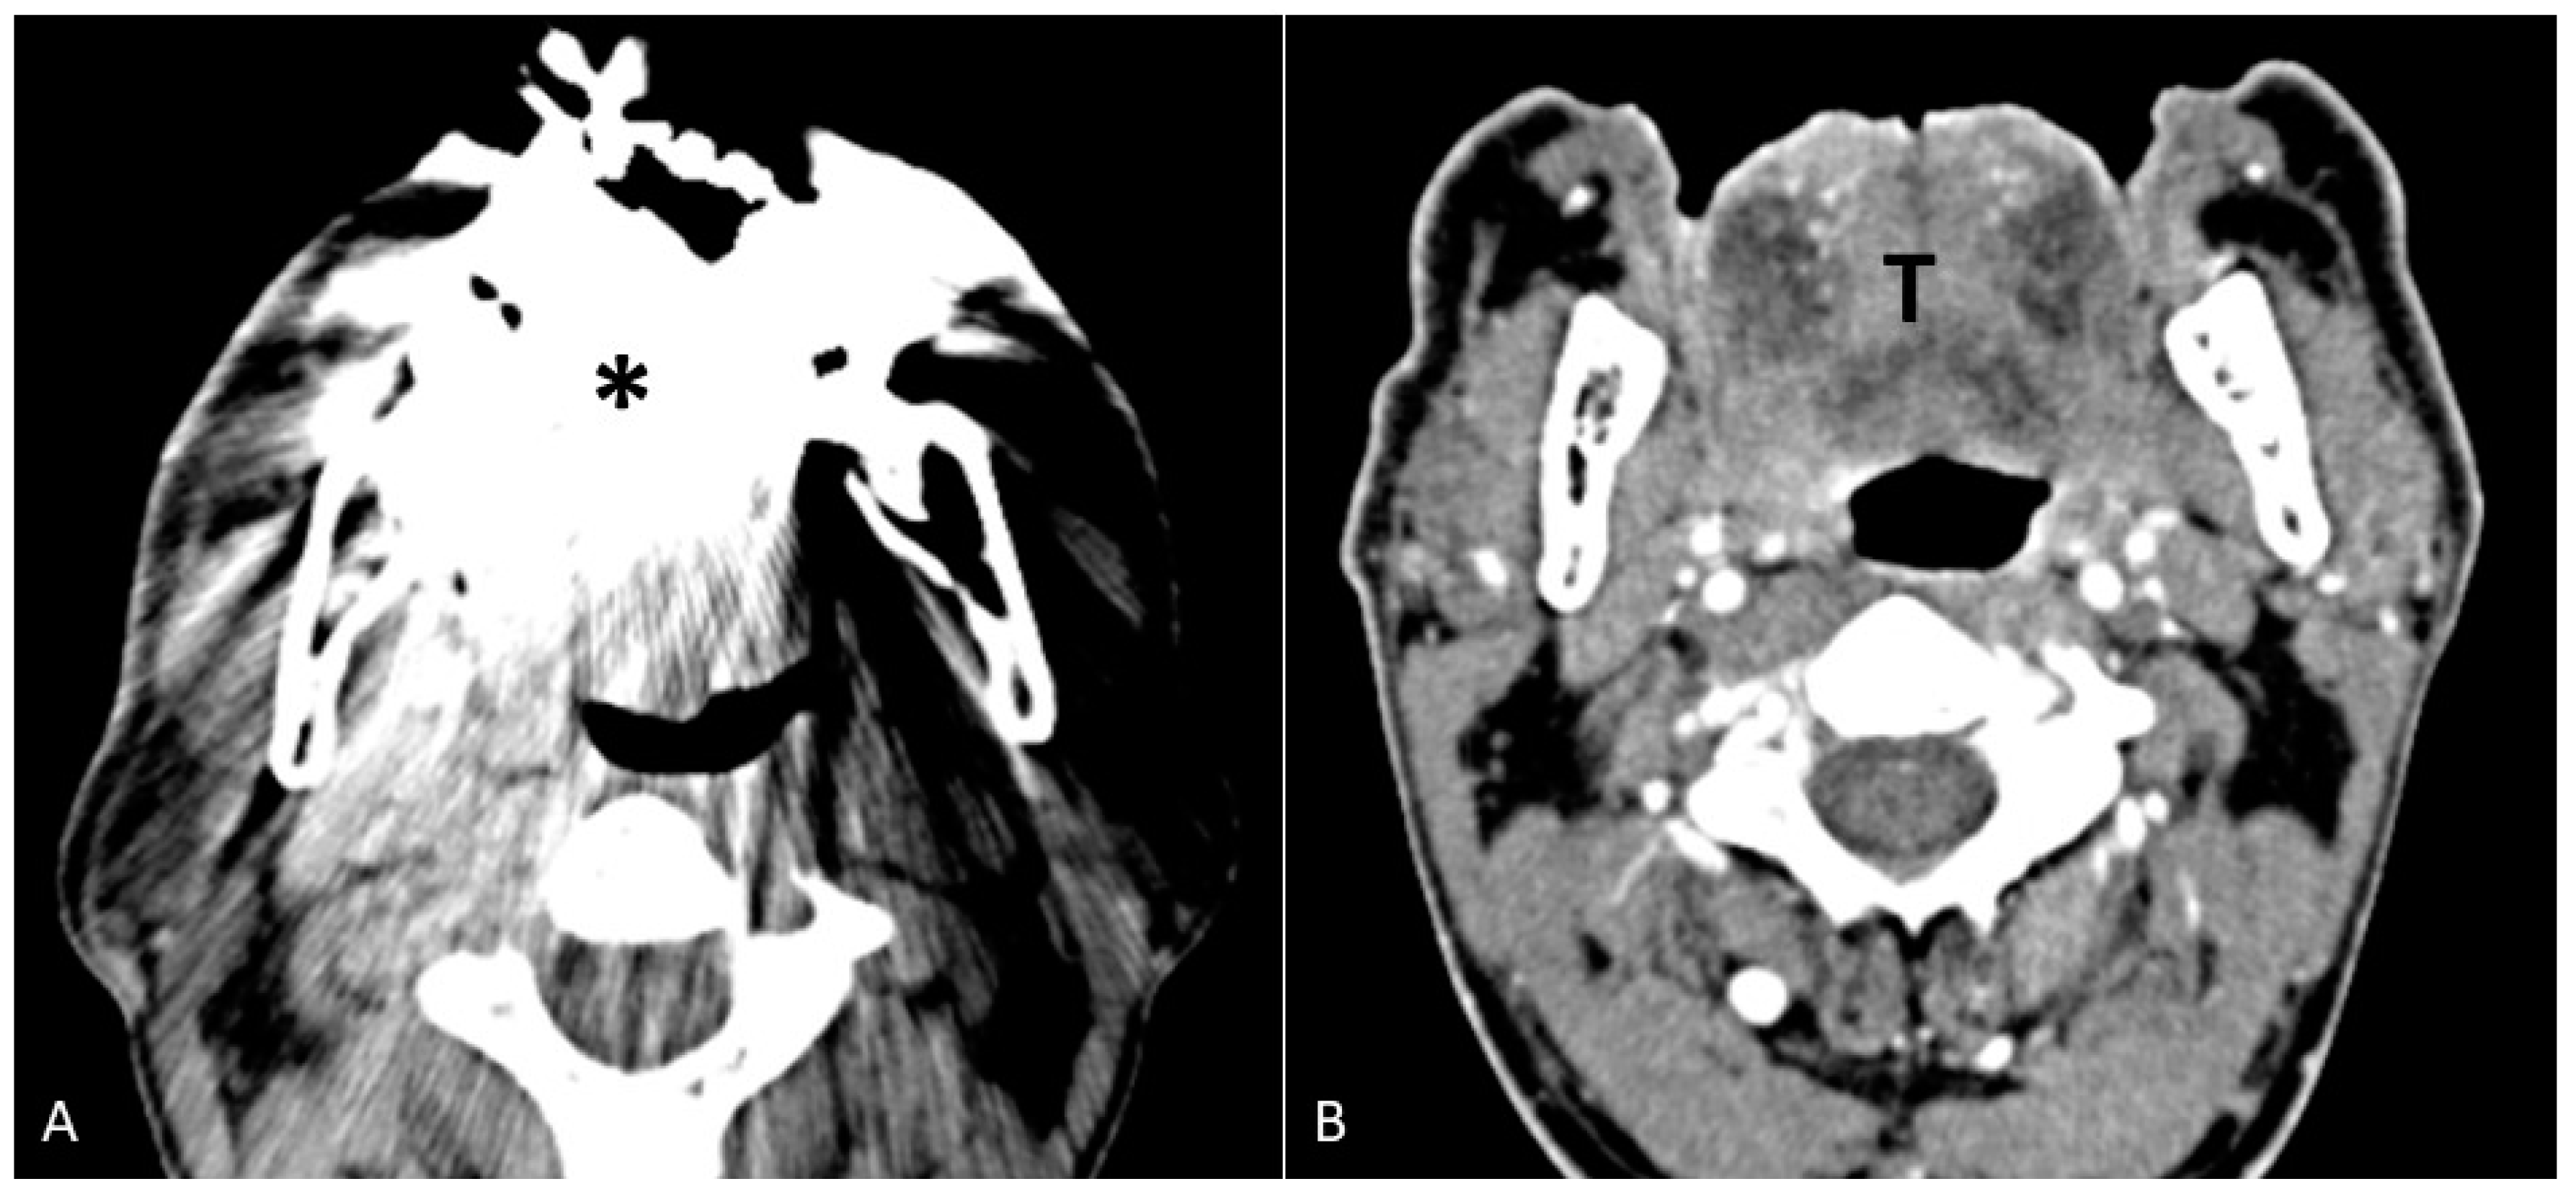

- Puffed cheek technique. The vestibule of the mouth is a virtual cavity due to the contact between the mucosa of the lip, cheek, and gingiva. Puffed cheek technique helps to determine if the lesion is arising from the buccal, gingival, or lingual mucosal surface since patients blow uniformly through pursed lips and the mucosal surfaces appear separated from each other. Therefore, the vestibular cavity can be appreciated as an air-filled horse-shoe-shaped space both on MSCT and MRI (Figure 10 and Figure 11).